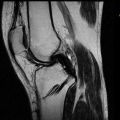

История лечения д-ра Гнелицы

Обратились к доктору Гнелица Николаю Николаевичу с травмой – разрыв крестообразной связки. Доктор пообещал успешную операцию и достаточно быстрое восстановление. После проведенной операции, через две недели снял швы. Через три дня после этого в месте проведения операции началось нагноение, образовалась гематома, поднялась температура, начался озноб. Т.е. начались признаки остеомиелита. Несмотря... Ещё Обратились к доктору Гнелица Николаю Николаевичу с травмой – разрыв крестообразной связки. Доктор пообещал успешную операцию и достаточно быстрое восстановление. После проведенной операции, через две недели снял швы. Через три дня после этого в месте проведения операции началось нагноение, образовалась гематома, поднялась температура, начался озноб. Т.е. начались признаки остеомиелита. Несмотря на каждодневное уведомление доктора о характере гематомы, о покраснении, о повышении температуры, г-н Гнелица не предпринял никаких мер для лечения постоперационной инфекции, а утверждал, что «это допустимая ситуация» (вся переписка сохранена, желающим можно ознакомиться). Прошел месяц, пытались лечиться антибиотиками, которые он назначил (назначил, не проведя никаких обследований). Через 1,5 месяца после операции гематома не проходит, доктор Гнелица назначил вторую операцию – чистка. Перед второй операцией не провел никаких исследований (должен был назначить МРТ и КТ), чтобы уточнить характер и глубину гематомы. Во время второй операции сделал достаточно глубокий разрез, как сам сказал, «все вычистил». К сожалению, из-за недостаточной подготовки доктора к операции (не провел никаких исследований, чтобы найти очаг инфекции), положительного результата операция не дала. Через неделю после второй операции гематома не проходит, покраснение, сделали МРТ и КТ, выяснили, что инфекция проникла в костную ткань. К сожалению, доктор Гнелица Николай Николаевич по-прежнему считает ситуацию «нормальной», он не провел необходимые анализы для того, чтобы определить очаг инфекции и наметить необходимые действия. Его рекомендации в этом случае – мазать мазью Вишневского (внутреннюю инфекцию). Он не замечает покраснения кожи, не замечает вздутия, не обращает внимание на озноб и повышение температуры. Мало того, он не считает нужным обращаться к другим, более опытным врачам, за консультацией.

Таким образом, мой отзыв о докторе Гнелица Н.Н. – отрицательный. Возможно, саму операцию он провел нормально, но оказался не компетентен в послеоперационном периоде, не смог справиться с инфекцией, которую, скорее всего, сам и занес.